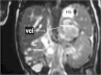

En la RM realizada 2 días después del ingreso, con el fin de valorar el territorio de la vena cava se observaba una masa suprarrenal izquierda de señal intermedia en T1 y levemente hiperintensa en T2, bien delimitada, que presentaba un halo periférico lineal hiperintenso en T1 y de baja señal en T2, y que no captaba contraste. Estos hallazgos concordaban con la existencia de una hemorragia suprarrenal izquierda en fase subaguda precoz. El riñón izquierdo estaba aumentado de tamaño, edematoso y con retraso tanto en la fase de captación como en la excretora. El riñón derecho era normal. Se observaba la ausencia de señal en la vena renal izquierda, que continuaba por la luz de la vena cava inferior sin afectarla por completo, lo que concordaba con una trombosis total de la vena renal izquierda y parcial de la vena cava inferior (fig. 3).